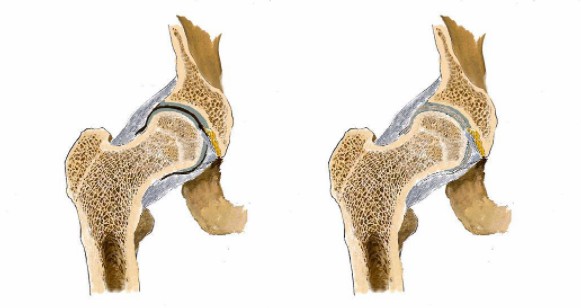

看男孩不說話,醫生繼續說道:“你的HLA-B27顯示陰性,如果是陽性就可以確診是強直性脊柱炎,現在只能排查……如果確診是強直性脊柱炎,就要就要及早治療,因為這個病是不可逆的,我們只能延緩它病程進度……”

醫生對著拍好的片子來來回回看了好幾遍,男孩就一直站在他邊上,他知道醫生接下來說的話將決定自己的一生。

“你這沒事!腿痛就是有點水腫炎癥導致的,注意休息鍛煉適度就會好的。”